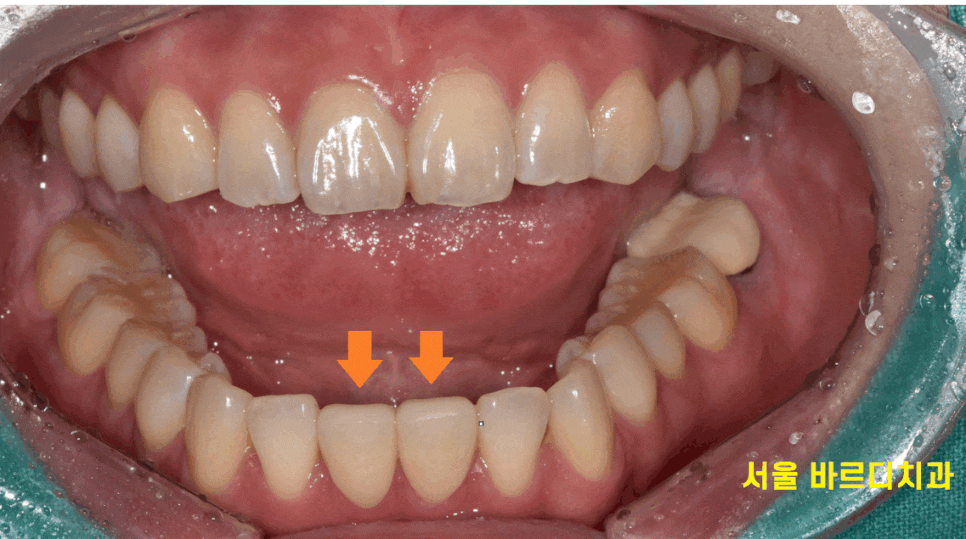

오늘 환자분은 윗니에 비하여

상대적으로 아랫니가 많이 벌어져 있었는데

벌어진 아래 앞니 4개나 되어

떼우는 레진 치료를 시행할 경우

치아가 너무 뚱뚱해 보일 가능성이 있었습니다.

또 다른 문제점으로는 양쪽을 다 떼워야해

작은 충격으로도 쉽게 떨어질 수 있었습니다.

두가지 문제점으로 앞니 라미네이트가 적합할 것 같다

추천 드렸는데요.